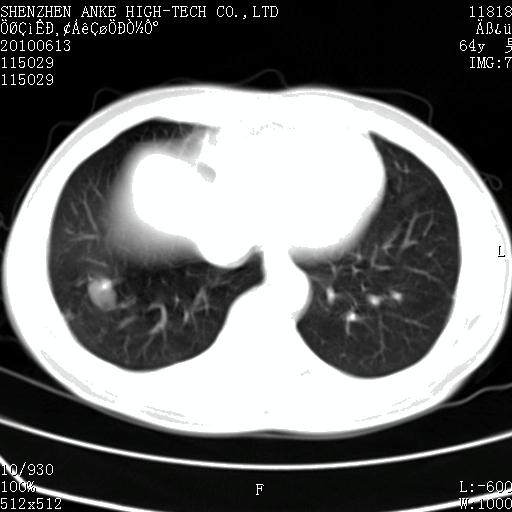

以下是引用beifangren在2010-7-26 22:05:00的发言:[br]左肾中极圆形占位,肾盏肾盂受压移位,建议增强。结合肺部结节。肝低密度灶,多为肾癌并肺部、肝转移。